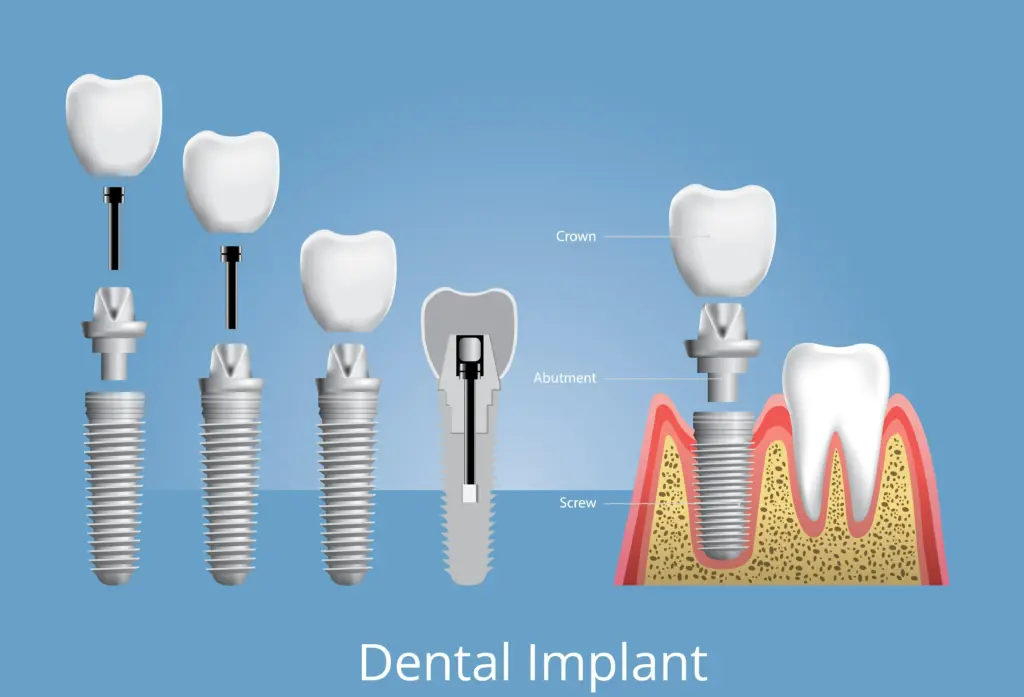

- Restorative phase: abutment and custom crown or bridge, including laboratory fees.